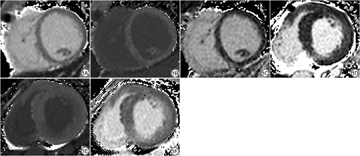

HHD组LAEF、LVEF均低于对照组(图1、2),LAEDV、LAESV、LVEDV、LVESV高于对照组,具体数据见表2。LGE示4例HHD患者存在条状或小片状延迟强化,而12例HHD患者未见确切延迟强化。其中10例出现二尖瓣返流,4例出现主动脉瓣返流,1例出现心肌脂肪浸润,未出现心肌梗死病例。

心肌细胞外容积:将对比剂注射前后的T1map DICOM图像导入心脏后处理分析软件(CVI42 v. 5.14.0 Circle Cardiovascular Imaging, Calgary, Canada)的T1弛豫模块,勾画出心腔内感兴趣区(region of interest, ROI)以计算红细胞容积,然后计算得出ECVmap,在ECVmap图像上分别勾画心底、心肌中层、心尖三个层面上室间隔、左室前壁、左室侧壁、左室下壁区域一共12个ROI,获得相应的ECV值,具体公式如下:

HHD组的ECV和pre-T1值明显高于对照组,具体见表3。